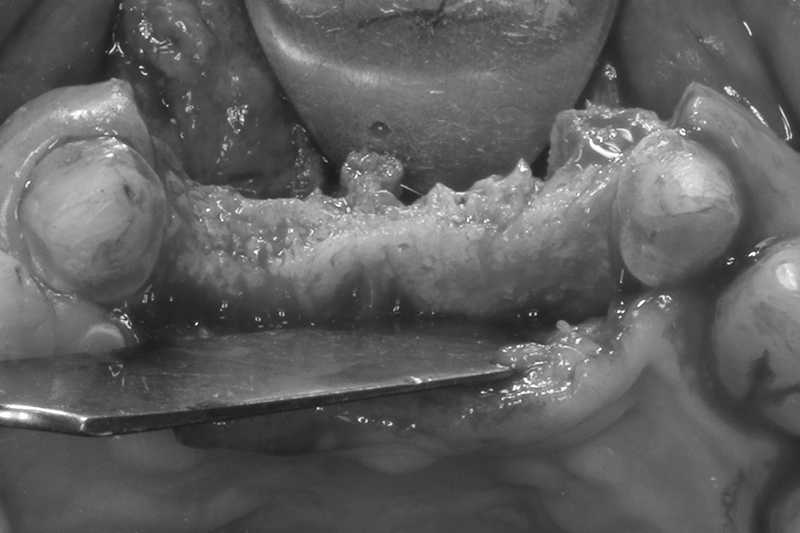

取出的舊有one piece植體,舊式植體。

接續牙周治療完成後的療程,上排門牙植牙的問題處理,長期不斷的發炎化膿流血,除了造成周圍組織發炎與牙齦腫脹,同時造成齒槽骨被細菌破壞與吸收,根本解決的方式是建議移除感染與位置不佳的植體,先進行植牙移除手術+齒槽骨保存術,先使用膠原蛋白促進軟組織癒合,加快癒合的速度。